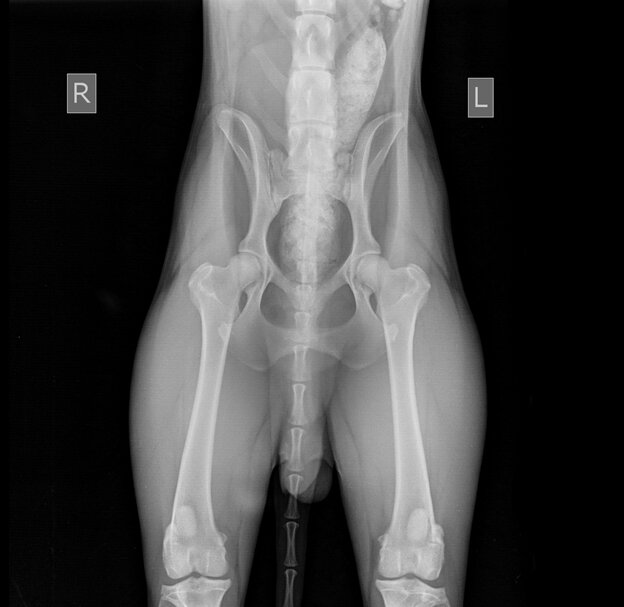

Тазобедренные суставы в норме